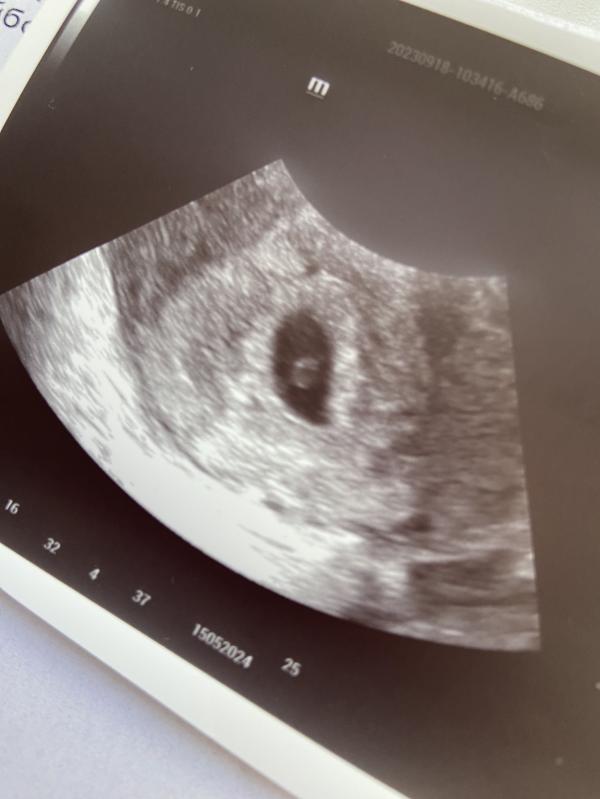

Сходила на первое свидание со своим комочком🥰

Все хорошо, эмбриончик еще совсем крошечный, но соответствует сроку🙏🏻 его даже аппарат узи не определял как эмбриона😅 но узистка отличная, нашла таки малыша, сердцебиение определяется🥰

Какая прелесть 💋 сколько вам тут неделек?